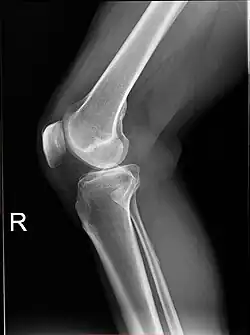

X-ray

-

Knee X-ray -

Knee X-ray (weight bearing) -

Knee X-ray (weight bearing, flexion)

Fractures

Knee fractures are rare but do occur, especially as a result of a road accident. Knee fractures include a patella fracture, and a type of avulsion fracture called a Segond fracture. There is usually immediate pain and swelling, and a difficulty or inability to stand on the leg. The muscles go into spasm and even the slightest movements are painful. X-rays can easily confirm the injury and surgery will depend on the degree of displacement and type of fracture.